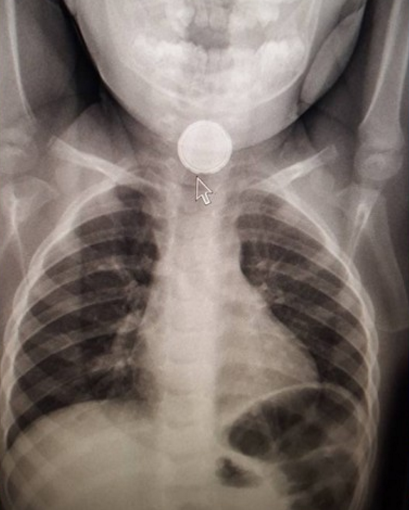

2歲女孩電池卡喉 被多名醫生診斷成流感

城市新聞電視截圖

據680新聞報道,2歲女孩Katie Smith不慎吞下電池,但四天后才被發現,這之前多家醫院和診所診斷她患了流感。

一周以前,小女孩開始不喝湯不吃餅乾,一直在作嘔咳嗽,父親Michael Smith知道有什麼不對,他和妻子Christina馬上帶女兒去了Lakeridge Oshawa醫院急症部,醫生告訴他們小姑娘是得了流感。

他們相信醫生的判斷,但是回去后小女孩仍然無精打采,一直作嘔。

他們又帶女兒去了Ajax一家無需預約診所,也被告知是流感。他們的家庭醫生也這樣說,Markham-Stouffville醫院急症部的醫生也這樣說。

但是父親Michael感覺到情況不對。上週四,他帶女兒去了Rouge Valley Ajax-Pickering照了X光。這才發現真相。他們馬上去了病童醫院讓女兒接受治療。

上週一,女兒在父母不知情的情況下吞下了一枚3.7伏的硬幣型鋰電池。電池里的內含物尚未洩漏,但是外層已經開始腐蝕,在小女孩的食道里熔化。

父親含淚說,“電池洩漏可能會要了我們女兒的命。”

這對夫妻說,小女孩現在已經恢復正常,快樂玩耍。父親感到真的很幸運,好在電池還沒有燒穿女兒的食道。

目前不清楚小女孩是在哪裡找到這枚電池的。這對夫妻說,家裡的東西並不會亂放。

他們希望其他的父母如果感覺到有事情不對時,要信任自己的直覺,一定要找到答案。

城市新聞聯繫了Lakeridge Oshawa,該醫院說未收到病人投訴,無法做出評論。Markham-Stouffville醫院則正對城市新聞獲取更多信息的要求進行處理。